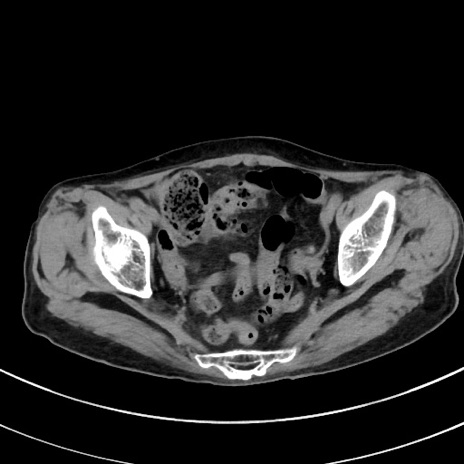

冠状断像